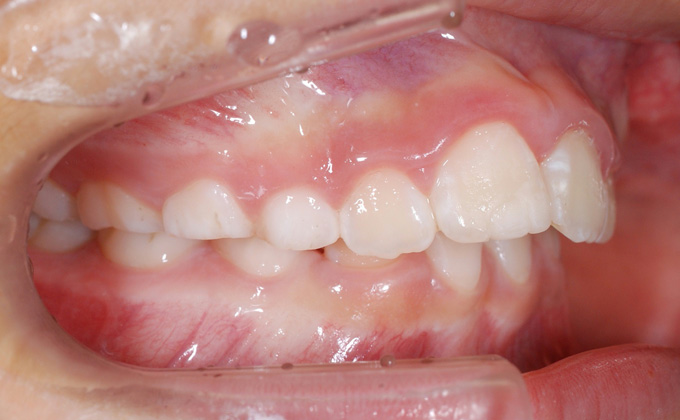

上顎前突(出っ歯)

上の歯が前に出ている状態を言います。歯が出ていると発音に影響が出ます。また折れたり唇を切ったりしやすく、見た目もあまりよくありません。